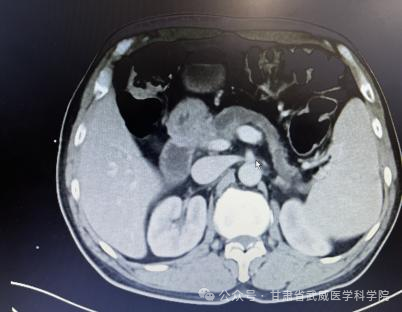

确诊时腹部CT资料

胰腺癌一经确诊没有手术根治机会平均生存期在三个月到半年左右,部分患者能够手术根治切除,术后总体五年生存率不超过5%。本病发病率男性高于女性,男女之比为1.5~2:1,男性患者远较绝经前的妇女多见,绝经后妇女的发病率与男性相仿。胰腺癌诊治困难主要在于其起病隐匿、转移迅速。武威肿瘤医院腹部外科凭借强大的技术力量,近日连续治疗了肝门胆管癌,胰腺癌等数例高难度患者,手术均成功实施,且患者均恢复顺利出院,我科2023年02月收治一例胰头部占位,经科主任仔细阅片、全科讨论后患者胰腺癌肿瘤侵犯门静脉(环周超过1800)及胃十二指肠动脉无外科切除机会,经过术前五周期全身静脉化疗(吉西他滨1000㎎/m2+白蛋白结合型紫杉醇125㎎/m2 D1、8)后CT评估该患者胰腺癌瘤体明显缩小,肿瘤与门静脉主干、胃十二指肠动脉之间有了一定的间隙,与患者家属积极交代病情及沟通后于2023-7-为该患者施行“根治性胰十二指肠切除+I125粒子植入术”,现恢复良好,总生存时间已超过1年。